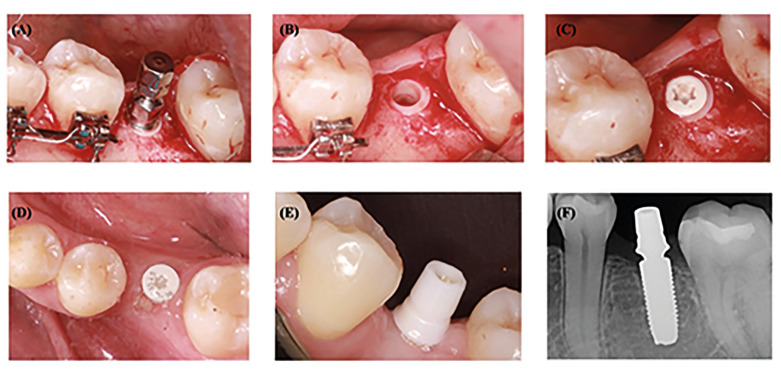

Results: Six studies met the inclusion criteria and were included for analysis, with a total of 298 T-PZI. A survival rate of 96.31% was recorded with follow-up periods ranging from 18.4±10.4 months to 111.1±2.2 months. The success rate ranged from 63 to 100% and MBL ranged from 0.130.6 to 1.38±0.81mm Conclusions: T-PZI may offer a reliable alternative to titanium dental implants, achieving a survival rate of 96.31%, acceptable rates of MBL and adequate biological parameters. However, the findings of the review must be treated with caution, as the data obtained are derived from the early stages of this new development in ceramic dental implants. More comparative studies are needed in order to determine the viability of T-PZI in different clinical situations.